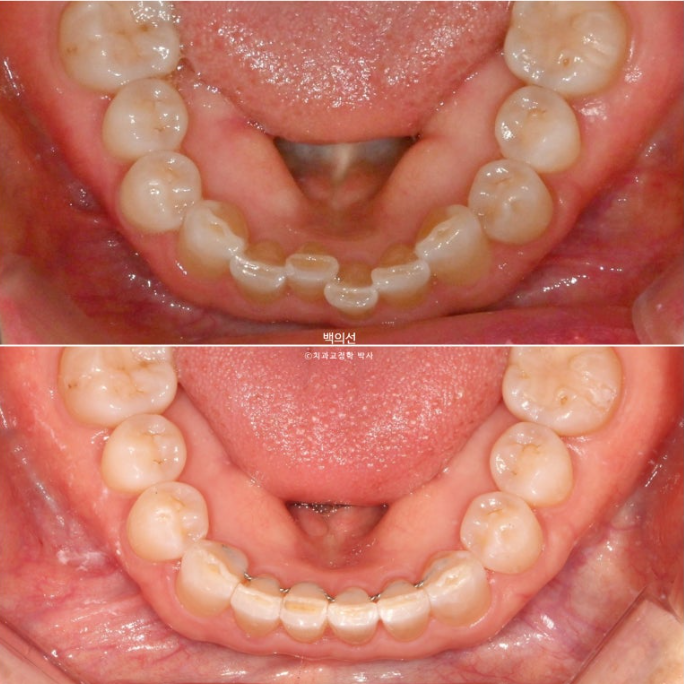

25.02

아래 앞니는 누구나 나이가 들면서 점점 틀어집니다.

앞니를 잡는 뼈가 약해지기도 하고, 평행에 걸쳐 교합력이 어금니들을 앞으로 밀어내는 방향으로 작용하기 때문입니다.

아직 많이 안 틀어졌을 때 배열을 한 번 잡아주는 것이 좋습니다.

아래 앞니 배열은 벌써 가지런해졌습니다.

재제작에 들어갔고 추가장치를 기다리는 1달간은 7번 마지막 장치를 잘 때만 끼면서 배열을 유지합니다.

25.08

25년 5월부터 7월까지 7개 추가장치를 모두 낀 후 치료를 마쳤습니다.